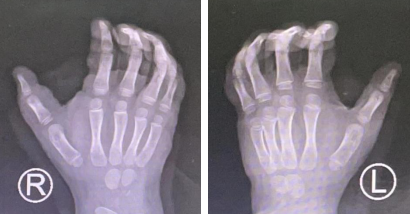

术前X线

今年1月初,一位妈妈带着孩子来到小儿骨科门诊,妈妈告诉接诊的贺敬坤医生,小孩双手大拇指都出现一个圆疙瘩,摸着硬硬的,以前很小,现在小孩长大了它们也跟着长大了。当时贺医生心里十分警惕,这些症状和骨肿瘤症状很相似,难道是手部骨肿瘤么?但随着和家长交谈、询问病史、仔细查体后这份疑虑慢慢放下了,原来孩子自出生时双手拇指均多出一根手指,当时家长内心十分焦虑。随后在孩子出生十几天后,他们选择做了多指的切除手术,本以为把这些不美好扼杀在摇篮里了。然而却没想到随着年龄的增长,到孩子1岁时,妈妈发现其双手拇指桡侧又各长出一圆形凸起,并伴随孩子生长发育一起生长,程度逐渐加深。到孩子5岁时更加明显,妈妈十分担心,经过多方打听后决定来到我院希望得到更好的治疗,最后通过完善相关检查确诊为左拇指畸形IV型,右拇指多指畸形III型。

拇指多指的分类,目前采用以解剖形态异常为基础的Wassel分类法,共分为7型。

III型指的是近节指骨分叉型,特点为近节指骨分叉,分别于重复的远节指骨形成关节,近节指骨与掌骨头之间有正常的关节,重复指可发育正常、退化或发育不良。IV型指的是近节指骨复指型,特点为各有独立的骨骺,与轻度变宽的掌骨头相关节,重复指骨纵轴交叉。